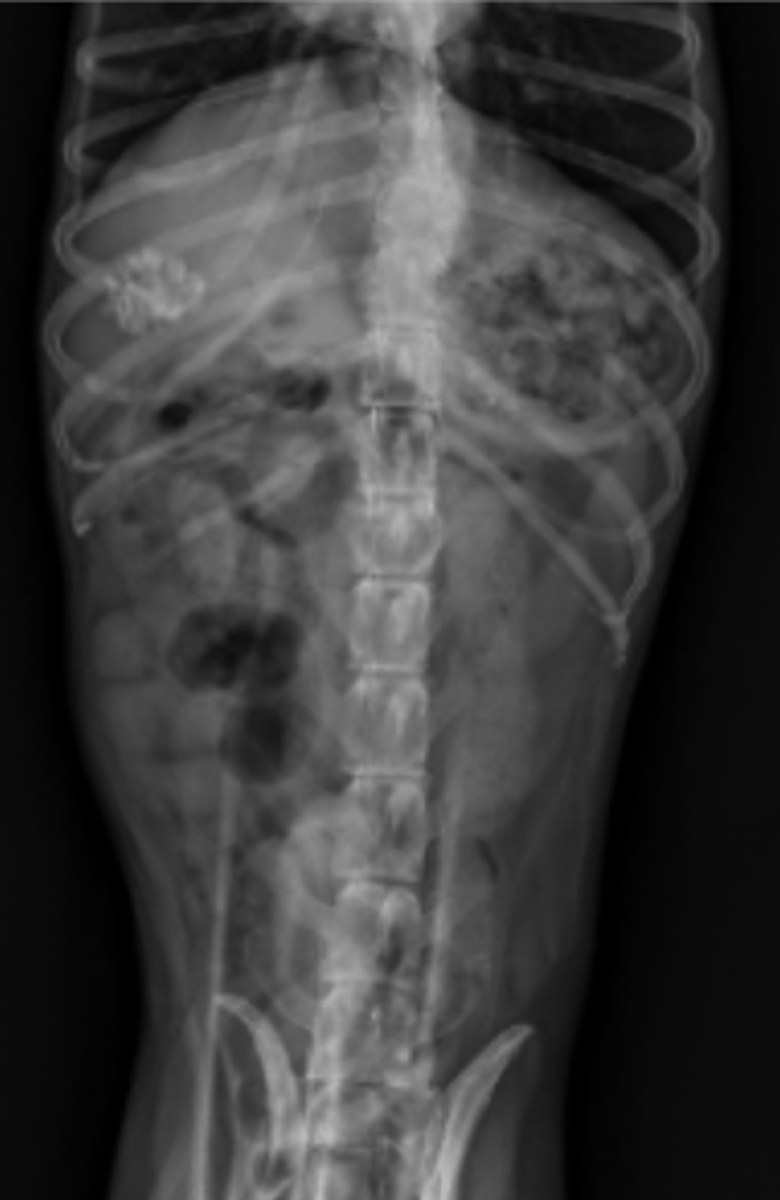

intususcepción

patología: